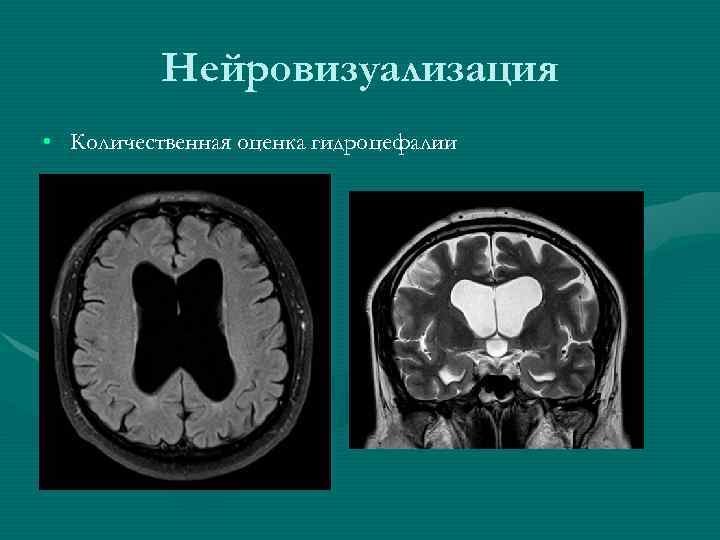

Нейровизуализация • Количественная оценка гидроцефалии